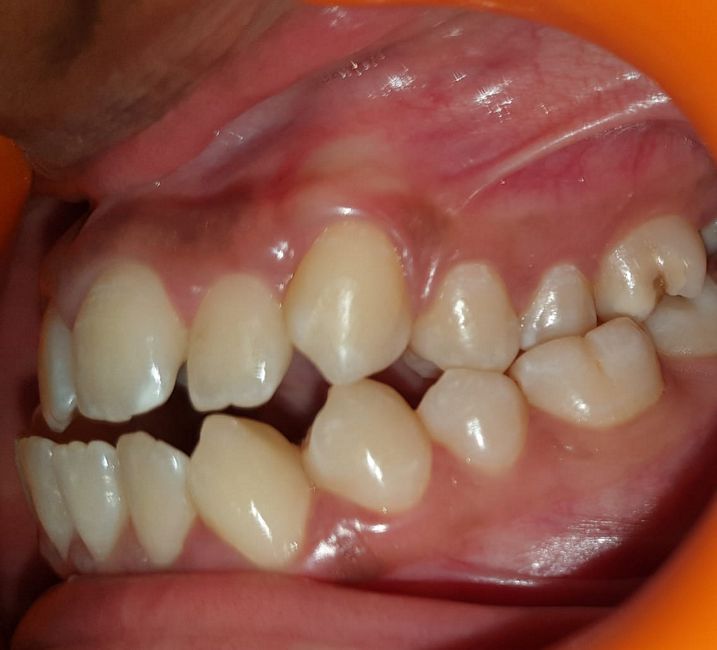

Case No: 15

Malocclusion Type: Skeletal Class II Malocclusion with Overjet of 10mm and Overbite of 7mm Mechanics: MBT Appliance (3M Metal Brackets)(Note: No Functional Appliance Used)

Intra-oral : Pre-treatment : Right Lateral View

Intra-oral : Pre, Mid & Post-treatment : Right Lateral View